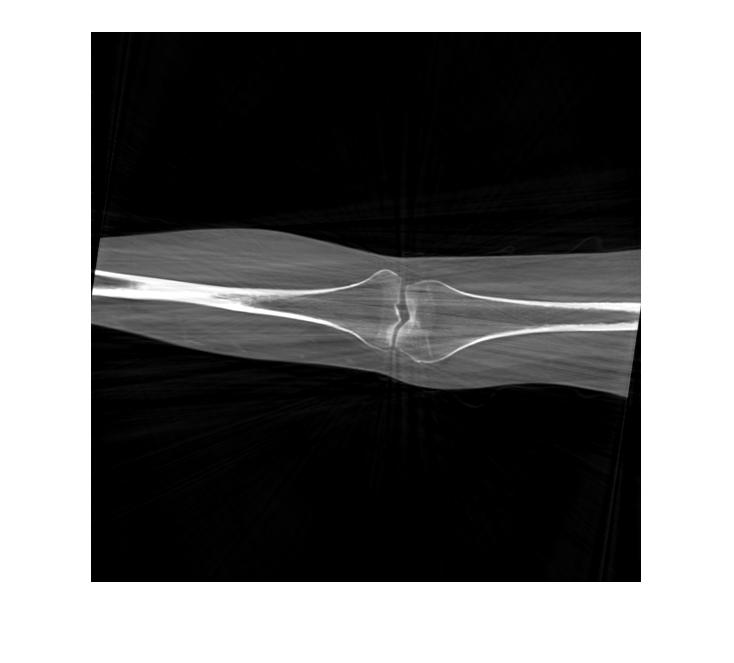

We test our algorithm on the tomographic reconstruction of two objects. The first is the Shepp–Logan phantom, and the second is a computed tomography of a knee taken from Ref. [32]. See Figure 5.6. In this experiment, we generate random points uniformly distributed in . The parameters used in Algorithm 3 are , and . The tomographic projections are computed using Matlab ‘s radon function. We add random noise to these projections, for that, we consider the dataset of the form

In Figures 5.9 and 5.10, we plot the reconstructed images of the Shepp–Logan phantom and the knee tomography, respectively. Here, the samples of the angles are uniformly distributed over . We consider different levels of additive order error as represented in Eq. (5.16). We remark that we obtained similar results to those shown using multiple executions of our method. To measure the effectiveness of our method, we compare the error generated when our algorithm is implemented. The computed error is shown in Tables 1 and 2. Observing the computational error and image quality, we conclude that our reconstruction algorithm works efficiently with relatively low computational cost.